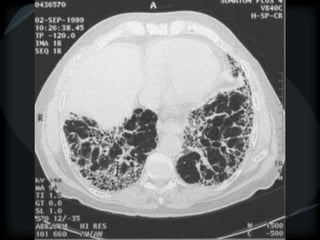

METS

random

miliary